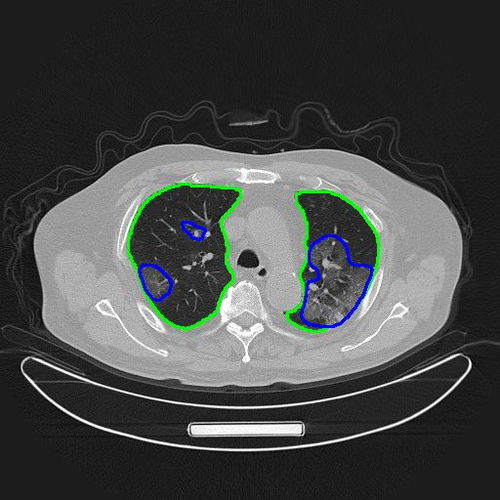

肺炎ct图片

肺炎胸片

ct片子图片